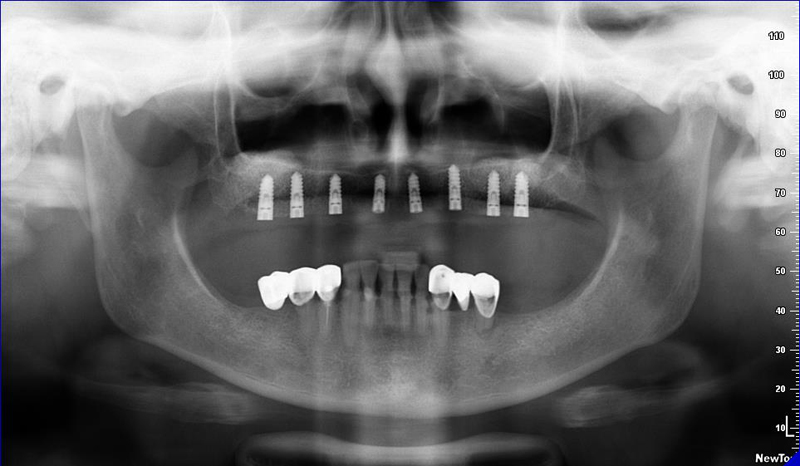

Lékař si vytvoří všechny typy zobrazení potřebných pro naplánování – tedy 2D snímky (panoramatický), příčné řezy i 3D model.

Vidí zde i důležité anatomické útvary – čelistní dutinu, průběh nervu atd. Po proměření množství kosti – šířky i výšky vybere z databáze vhodný typ implantátu a umístí ho do požadované lokality. Ihned vidí jeho pozici ve všech 3 rovinách a na všech snímcích i 3D modelu. Může upravovat podle potřeby jeho pozici, sklon atd.

Všechny vybrané a správně umístěné simulované implantáty se ukládají do „počítačové karty“ pacienta s jejich pozicí, délkou, průměrem, typem i sklonem. V programu také lékař navrhuje chirurgické šablony pro řízenou nebo navigovanou implantaci. Lékař i pacient tedy ještě před vlastní operací vidí, jak by mělo ošetření probíhat a vypadat.

2) CB CT scan s modelem náhrady

8) Kontrolní RTG snímek po operaci